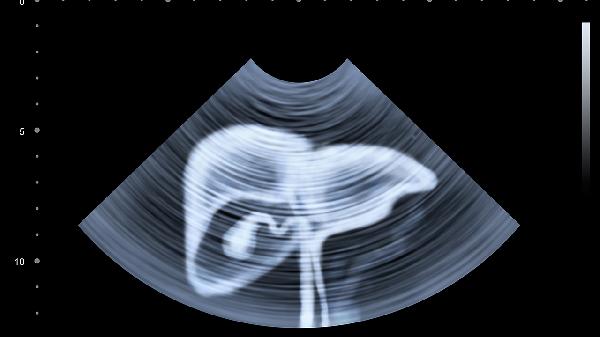

乙肝、丙肝病毒攜帶者,肝硬化患者需要每3-6個月做一次超聲和甲胎蛋白檢查。

每年至少做一次肝功能檢查和肝臟超聲,高危人群要縮短檢查間隔。